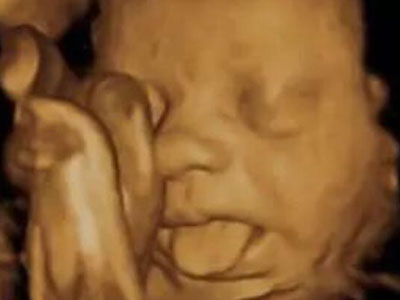

扮鬼脸

胎宝宝在娘胎里就是“戏精”:吸吮手指、啃脚丫、吧唧嘴、抠鼻子、吐舌头、微笑、皱眉......表情贼丰富了!妈妈第一次给胎宝宝做四维彩超时有没有惊讶到?我那会儿开心死了!原来,他很早就学会表达自己的感受了,还真是人精!